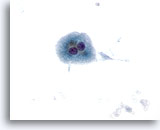

画像 4

肝FNA – 良性肝細胞

反応性変化を来した肝細胞。核は大小不同で、二核を有しています。

40倍

画像 4

肝FNA – 良性肝細胞

反応性変化を来した肝細胞。核は大小不同で、二核を有しています。

40倍